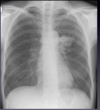

19

Right middle lobe pneumonia

-Silhouette sign of right heart border opposite can no longer be discerned, so we can predict that the right middle lobe is involved.

-Note that the right diaphragm remains visible.